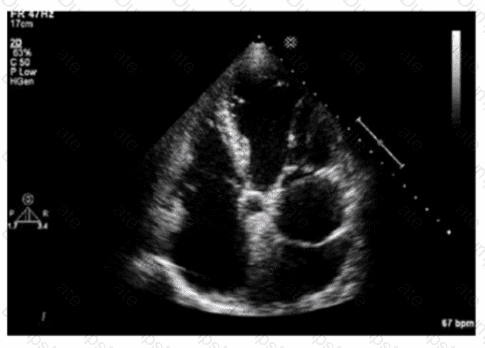

Questions 5

Which pathology is consistent with the left ventricular strain pattern shown in this image?

AE-Adult-Echocardiography Question 5

Options:

A.

Amyloidosis

B.

Apical hypertrophy

C.

Non-ischemic cardiomyopathy

D.

Right coronary artery infarct